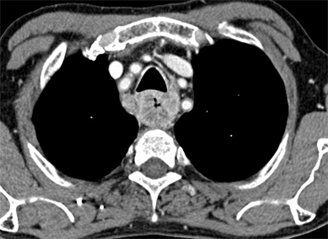

Esophageal cancer as seen on CT; source: Hellerhoff, Wikimedia Commons